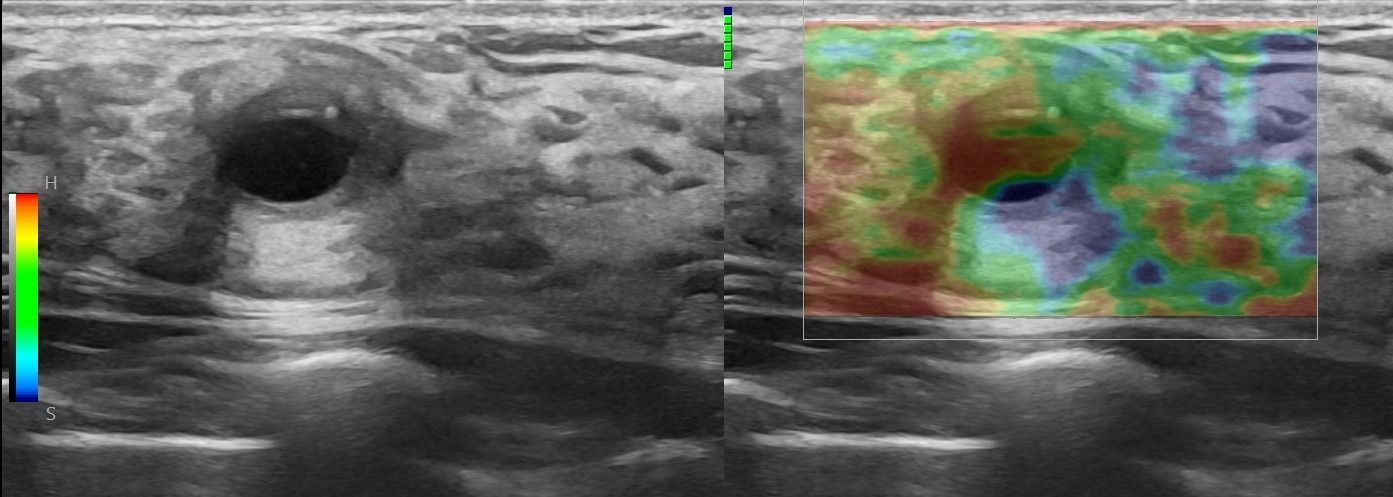

Elastography: The Additional Advantage in Breast Ultrasound

Modern ultrasound machines, equipped with advanced high-frequency transducers, techniques such as Color Doppler, Power Doppler, B-Flow, and Elastography, allow the analysis of breast architecture with exceptional accuracy.

Elastography can highlight the elasticity of a lesion, indicating whether it is hard or soft. Through this technique, we can assess the nature of the lesion, providing indications of whether it is benign or malignant. Additionally, with the contribution of Color Power Doppler and B-Flow, we can monitor the vascular flow within the lesions, offering even more information about the type and nature of the abnormality.